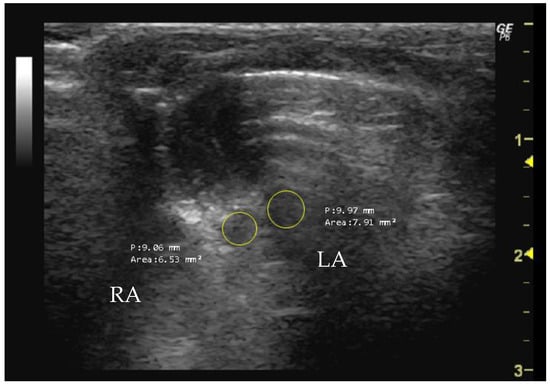

- How to measure RA and LA

Apical Five-Chamber View